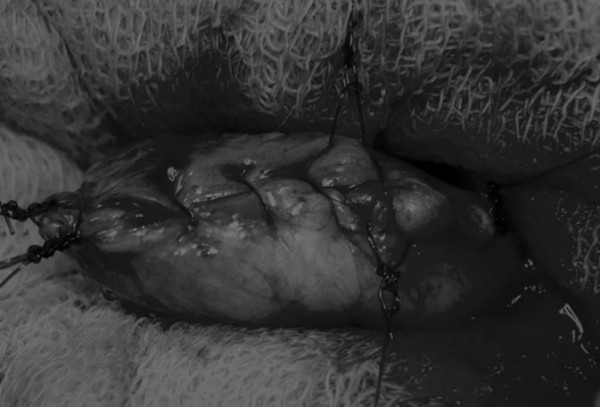

在牵引缝线之间选择血管扩张较差的区域用手术刀切开膀胱壁(图3)。在牵引缝合线之间用手术刀在血管不良的区域做切口。切开膀胱壁后,膀胱内的手术可按手术方案实施,例如取出结石(图4)。

图3 避开主要的膀胱血管,做一个尽可能小的切口

切口可以在膀胱背侧或腹侧进行,避免对大血管的损伤。

图4 这张图显示了从膀胱中取出的大量结石